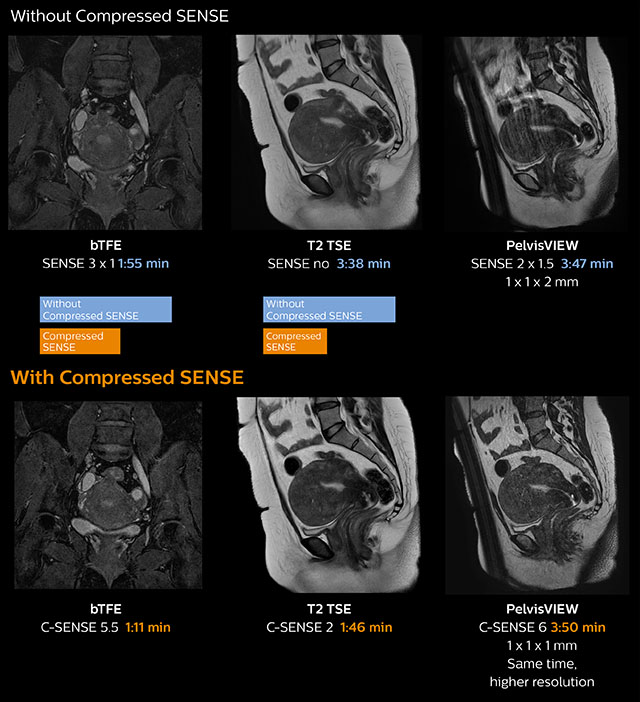

In this MRI exam of pelvis in a patient with myoma, Compressed SENSE is used to accelerate individual sequences and thus the entire examination on Ingenia 1.5T. Compressed SENSE allowed for a decrease in scan time for the T2 TSE from 3:38 to 1:46 minutes. The Compressed SENSE images in this case show fewer motion artifacts than the images from the previous protocol with SENSE. In 3D PelvisVIEW, the Compressed SENSE images have a higher and isotropic spatial resolution with a scan time similar to the SENSE sequence. The improved spatial resolution and better contrast in the myometrium of the uterus allowed radiologist Dr. Koyama to confidently diagnose the cancerous lesion in the uterus. The use of Compressed SENSE accelerates scanning times and increases spatial resolution in 3D PelvisVIEW.